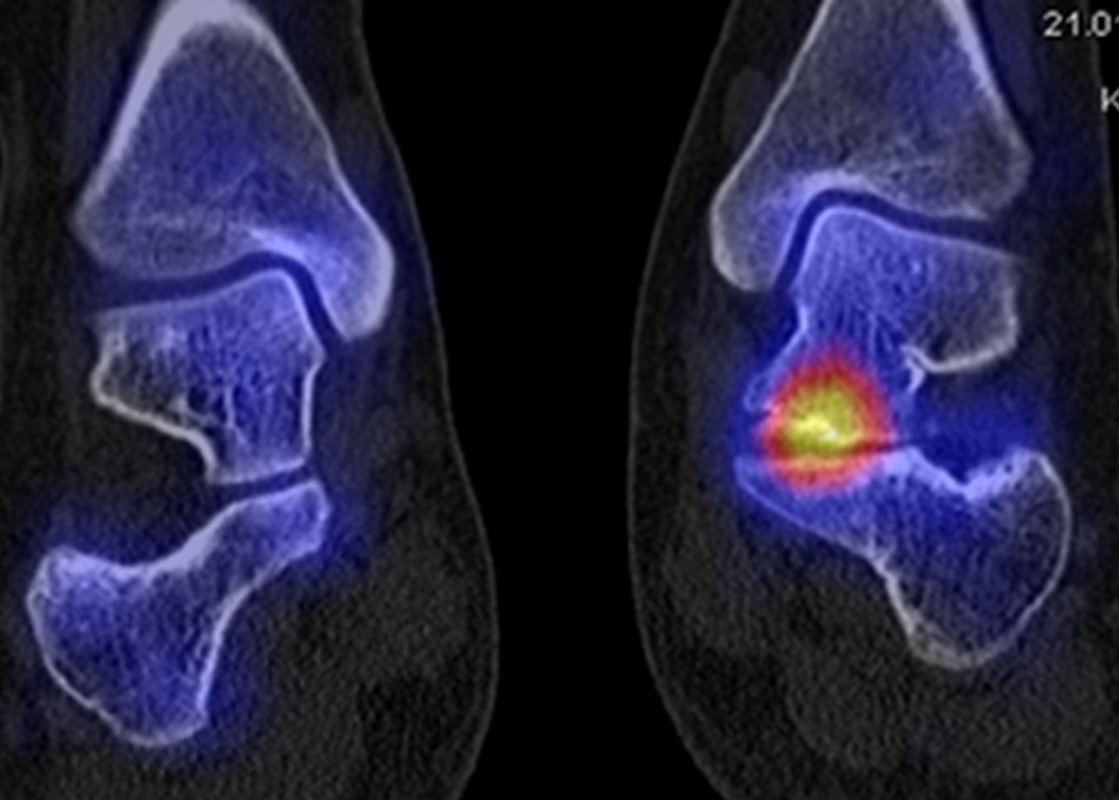

Abbildung 2.1.

Bildbeispiele symptomatische OCL

Zum Lesen der Bildbeschreibung und zur Vollansicht bitte das Bild anklicken. Bild: H. C. Rischke

Abbildung 2.2.

Bilder eines Patienten mit Z. n. mehrfachen Sprunggelenksdistorsionen in der Vergangenheit, besonders heftige Distorsion des linken Sprunggelenkes 5 Wochen vor der Untersuchung. Die SPECT/CT zeigt eine instabile osteochondrale Läsion mit deutlicher Aktivierung.

Abbildung 2.3.

Klärung bei Schmerzen im rechten OSG bei OCL an der medialen Talusschulter. Z. n. OSG-Distorsion vor 2 Jahren und Z. n. OSG-Fraktur / Syndesomosenruptur. Ausgedehnte OCL, hier jedoch kein erhöhter Knochenmetabolismus; lediglich Nachweis einer Stressreaktion im Bereich der Synchondrose eines Os trigonum als Schmerzursache.